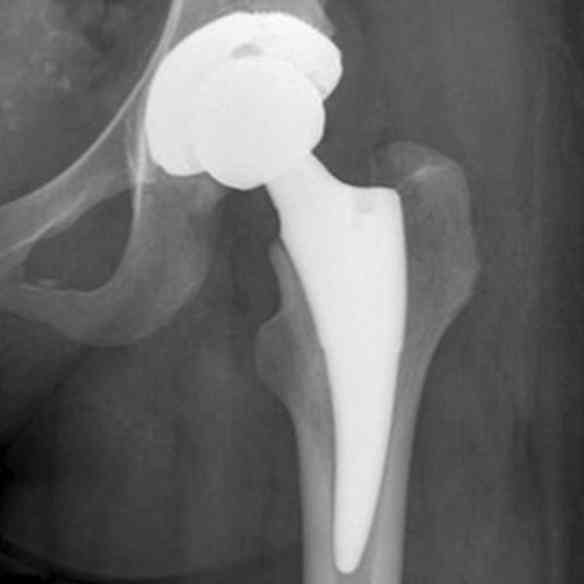

Erfahren Sie mehr über die sympatische Extremsportlerin Claudia Wenning (seit dem 17.07.2021 - vorher Weber), die mit zwei Hüftprothesen sportliche Leistungen erbringt. Bis 2010 war Sie auf den Laufstrecken der Welt unterwegs war und hat sich für die gute Sache mit selbst organierten Läufen eingesetzt. Dabei konnte sich fast 70.000 Euro an Spenden sammeln. Im Jahre 2011 endete die Läuferkarriere vorerst, da eine bis daher nicht erkannte (von Geburt an) Hüftdysplasie festgestellt wurde. Mittlerweile hat Claudia 2 Hüft TEP's und läuft Strecken bis Halbmarathon und ist aber nicht müde sich weiter für andere Menschen einzusetzten. Klicken Sie sich durch Ihre Webseite oder treten Sie mit mir in Kontakt.

Ab 2018 ist Sie mit zwei Hüft TEP's auf den Laufstrekcne bis maximal Halbmarathon, sowie im Triathlon Bereich unterwegs.